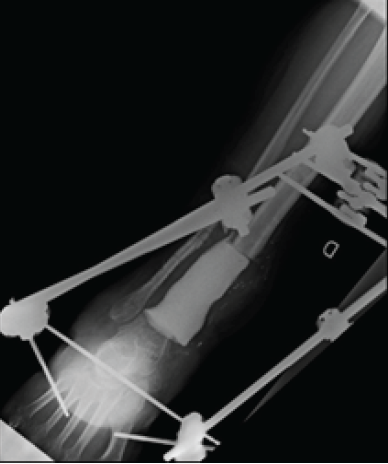

The patient was managed surgically with lifting of the covering flap using a lateral surgical approach, removal of the material from the lateral malleolus, osteotomy of the fibula, resection of 9 cm of distal tibia involving the metaphysis and the epiphysis, intramedullary curettage of the tibia at the section area, filling with a cement PMC and Hoffman-type external fixation (Fig. 4).

Figure 4: Bone distal tibia resection, external fixator and filling with polymethyl methacrylate.